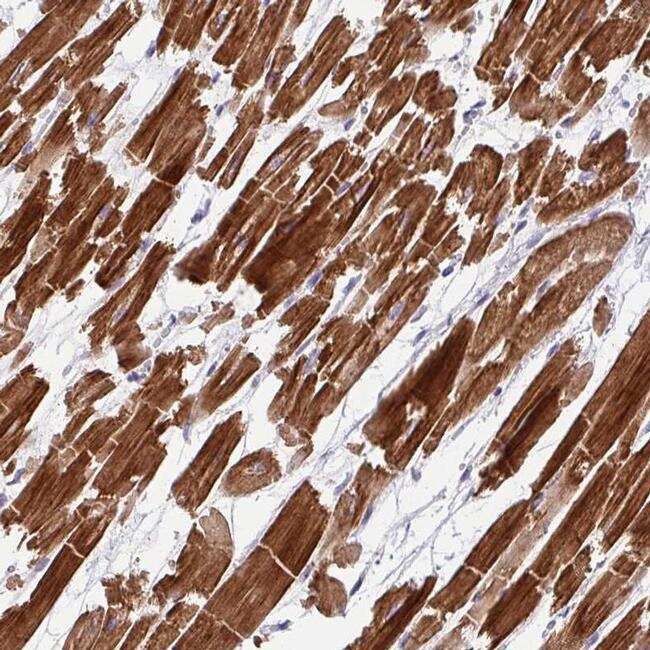

- Immunohistochemical analysis of WDR38 in human heart muscle using WDR38 Polyclonal Antibody (Product # PA5-63327) shows strong cytoplasmic positivity in myocytes.